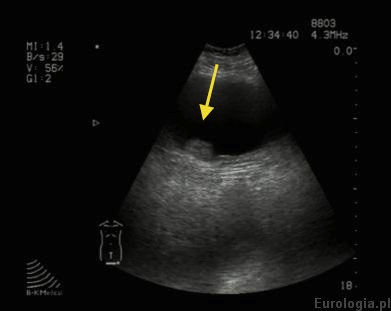

Guz pęcherza w USG

Fot. Guz pecherza okolicy ujścia prawego moczowodu średnicy 14 mm widoczny w USG

Obraz USG guza pęcherza moczowego

Obraz USG guza pęcherza moczowego